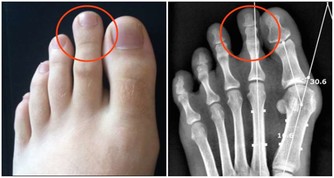

4.運動少,血管垃圾多

下肢血管也很重要,但常被大家忽視。多運動能讓更多的毛細血管開放,促進血液微循環;而長期不運動,血管內的垃圾會逐漸累積,形成粥樣硬化斑塊這個「不定時炸彈」,還會影響到毛細血管供血,並且隨時可能被引爆。